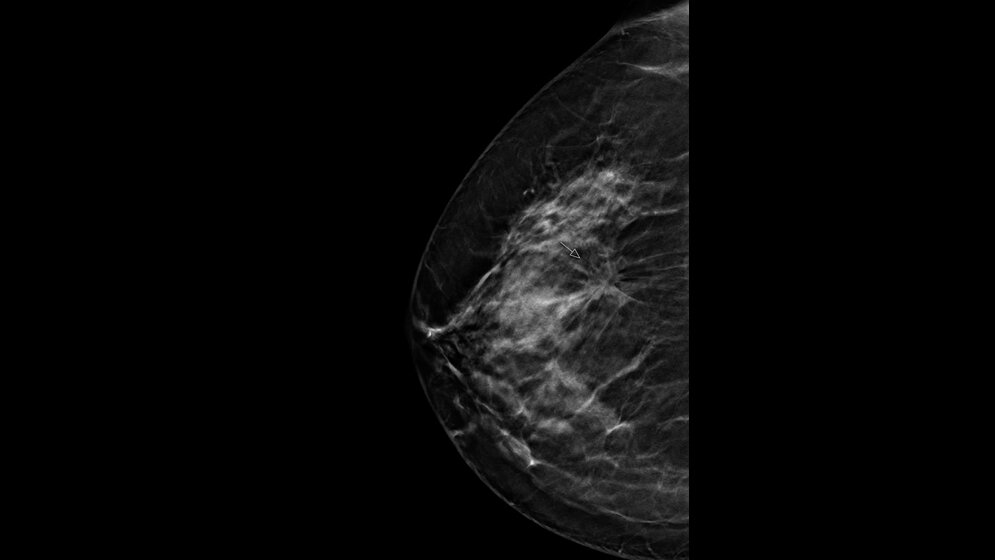

Führt die Verbesserung digitaler Techniken zur Früherkennung von Brustkrebs auch zu Effizienzsteigerungen im Mammographie-Screening? Diese Frage steht im Fokus eines groß angelegten Forschungsprojektes der Radiologie am Universitätsklinikum Münster (UKM): In der sogenannten ToSyMa-Studie wird geprüft, ob die technische Weiterentwicklung der digitalen Mammographie zum Schichtbildverfahren (digitale Brust-Tomosynthese) den derzeitigen Standard der zweidimensionalen mammographischen Brustuntersuchung im Screening voranbringt. Geplant ist, 80.000 anspruchsberechtigte Frauen zwischen 50 und 69 Jahren, die sich für eine Teilnahme am Screening entschieden haben, für die Datenerhebung zu gewinnen. Die von einem interdisziplinären Team der Universität Münster entwickelte diagnostische Studie wird von der Deutschen Forschungsgemeinschaft (DFG) gefördert.

„Mit der Weiterentwicklung der digitalen Mammographie zur Brust-Tomosynthese steht eine Technologie zur Verfügung, die durch die Berechnung dreidimensionaler Datensätze potenzielle Gewebeüberlagerungen in der Brust reduziert und daher diagnostische Vorteile bieten kann. Erste Ergebnisse aus ToSyMa werden Ende 2020 erwartet, abschließende im Jahr 2023“, sagt Prof. Walter Heindel, Direktor des Instituts für Klinische Radiologie (IKR) der Uniklinik Münster. Der Projektname ist eine Abkürzung und leitet sich ab aus dem englischen Titel der Studie („Digital breast tomosynthesis plus synthesised images versus standard full-field digital mammography in population-based screening“).